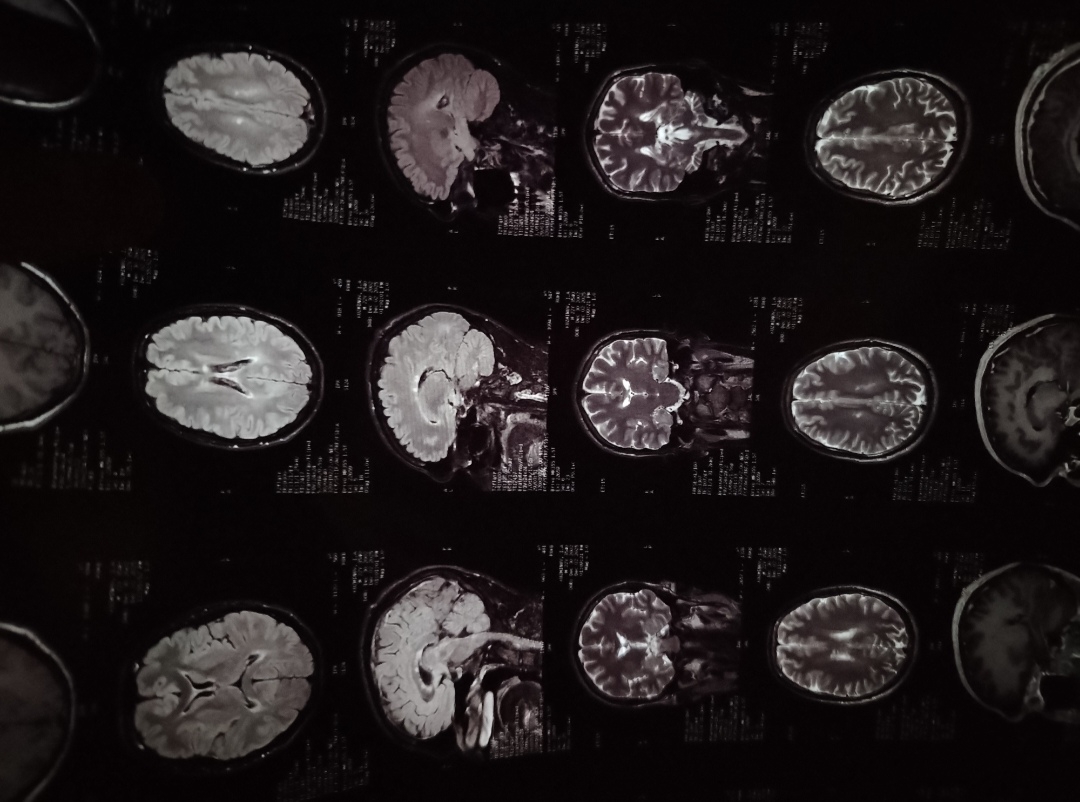

умирающий от гнили в голове

в заключении мрт написали что пиздец, но у меня комплекс симптомов

У чела рассеянный склероз, вероятнее всего

Жить будет, если уколы колоть

демиелинизирующее какойто степени. впадлу бумажки искать

хз, скоро пойду к неврологу и мне все озвучат. мртшные врачицы охуевали со снимков и ни на шаг не отходили после всех бумажек, что я им дал и после процедуры мрт они за мной ходили и за ручку держали

сказали что пиздец

Снимок чей? Какую то субдуральную гематома разве что заметил. С такой хуйней до старости доживают.